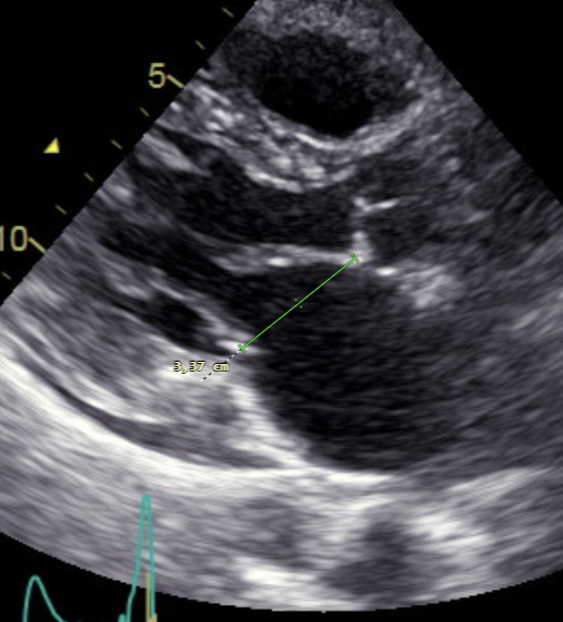

Echocardiographic assessments of the mitral valve were conducted using a Vivid E95 Cardiac Ultrasound and meticulously analyzed using the EchoPACTM and TOMTEC Imaging Systems. A crucial aspect of the examination involved measuring all components of the mitral valve and determining the requisite angles to evaluate each mechanism thoroughly.

Results: Most patients exhibited leaflet restriction as the primary cause of MR, with varying degrees of severity. Mitral leaflet morphology was categorized as normal in 15,8%, fibrodegenerative changes were in 31,5% and leaflet thickening in 52,7%.

In addition, outflow tract obstruction (LVOTO) was observed in 15,7% but without systolic anterior motion (SAM) and annular dilatation (dilatation of anteroposterior annulus more than 35 mm in systole) was present in 66%.